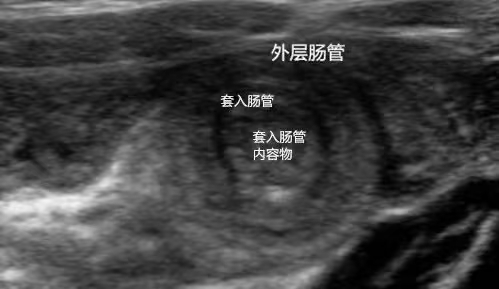

一、什么是肠套叠? 肠套叠是指一段肠管及其系膜套入与其相连的肠腔内,而引起的一种机械性梗阻,是婴幼儿时期常见的急腹症之一,亦是引起小儿肠梗阻最常见病因之一。肠套叠分原发性和继发性两种类型,原发性肠套叠更为常见,多见于2岁以内的幼儿,男孩发病率高于女孩。 二、肠套叠有哪些症状? 1.腹痛:这是最主要的症状,表现为突然发作剧烈的阵发性绞痛,患儿哭闹不安,间歇10-20分钟后伴随肠蠕动出现又反复发作。 2.呕吐:腹痛发作后不久就会呕吐,初期为反射性呕吐,吐出胃内容物,随着病情发展,可能会吐出胆汁样液体。 3.果酱样血便:在肠套叠发生一段时间后,出现典型的果酱样血便,这是由于肠管套叠后,肠壁血管受压破裂所致。 4.腹部肿块:在宝宝的腹部可以摸到腊肠样的肿块,位置多在右上腹或腹部中部。 三、如何确诊肠套叠? 超声检查是诊断小儿肠套叠的首选检查手段,具有无创、无辐射、可重复性高等多个优势,可以及时、准确地为确诊小儿肠套叠提供诊断依据。 肠套叠超声表现: 1、“同心圆征”或“靶环征”:横切面上,肿块呈靶环征或同心圆征,外圆为肠壁回声,内圆为套入部肠管、肠系膜及肠管内的气体回声。 2、“套筒征”:纵切面上,肿块呈套筒状,外层为肠壁回声,内层为套入部肠管回声、肠系膜和肠管内的气体回声。 3、超声检查除了明确是否存在肠套叠,亦可观察肠壁水肿程度及肠壁血运情况、套管内有无肿大淋巴结、近端肠管有无扩张等。 肠壁严重缺血时,超声也有较明显的特征:肠壁明显水肿增厚,肠壁回声减低,出现分层,肠壁上有时还可见不同程度液化无回声。 4、彩色多普勒血流显像:局部肠壁血流信号增多,可呈环状或半环状;当套入肠壁缺血坏死时,缺血部分肠壁血流信号减少或消失。 四、肠套叠治疗原则 及早行复位治疗(尽可能48h内): 1、X线空气灌肠复位; 2、超声引导水压复位; 3、手术复位:适用于复位保守治疗失败或怀疑已发生肠坏死。 最后,提醒各位家长:肠套叠是婴幼儿期最严重的外科急症之一,及时发现非常重要。一旦发现宝宝出现腹痛、呕吐、便血等症状,应立即就医,争取早期诊断和治疗,以保障宝宝的健康成长。超声检查作为临床的第三只眼睛,不仅能及时、有效的为临床提供有无肠套叠的诊断,还可评估治疗效果,查看灌肠后肠管是否完全复位。 科普医生简介: 柯婕妤 超声波医学主治医师。 2014年广东医学院临床医学全日制本科毕业,毕业后一直从事超声科工作,2022年分别到广东省妇幼保健院进修胎儿三维彩超、中山大学附属第三医院进修超声介入。广东省泌尿生殖协会超声分会委员、广东省女医师协会超声专业委员会委员、广东省医疗行业协会超声医学管理分会委员、阳江市医学会超声分会委员、阳江市医师协会超声分会委员。 擅长领域:擅长妇产科、腹部、浅表等超声检查。